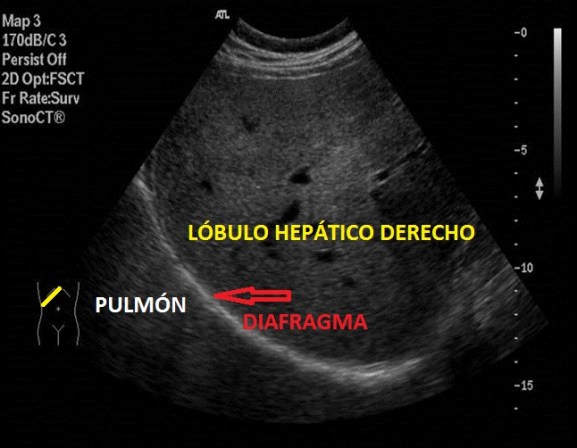

En el Post 48 vamos a estudiar el Lóbulo Hepático Derecho y vamos a escoger una imagen de esta región anatómica hepática donde podamos ver una mayor cantidad de superficie del LHD, donde veamos diafragma y donde veamos nítidamente los márgenes y delimitaciones del LHD y su especial relación con el pulmón derecho…

Esta imagen será vital para demostrar que el ángulo costofrénico derecho esté libre de derrames pleurales, que de existir, se verían como una cuña anecoica (lo estudiaremos en su momento) y que si la exploración es normal, se verá artefactado por la normal presencia de aire en el parénquima pulmonar locorregional. Algunos derrames pleurales son visto por primera vez en este tipo de protocolo, el/la Técnico siempre alerta ante cualquier cambio respecto de la normalidad.

El Diafragma se verá como una línea hiperecogénica lineal, curva y lisa. Mucho ojo con la presencia de el Artefacto de Espejo que es tremendamente habitual en esta localización, te pongo una enlace para que puedas repasarlo.

La imagen que perseguimos es esta:

Con la correlación anatómica lo comprenderás mejor…

Obsérvese la colocación correcta de la sonda en el pictograma en amarillo.

LHD Homogéneo con sus imágenes anecoicas correspondiente a vasos hepáticos.

Pulmón Derecho, área artefactada del ángulo costofrénico derecho.

Diafragma, que es la línea hiperecogénica que separa ambos órganos.

Si no indicamos nada, ninguna medida, ni señalamos nada que nos llame la atención y que tenga que saber el/la Radiólogo/a, queremos hacerle entender que en esa zona «todo está tranquilo»…